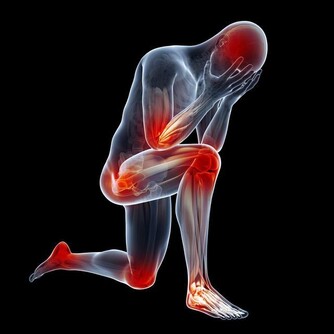

1.脂肪墊勞損 脂肪墊充填於膝關節前部的間隙,有加強關節穩定和減少摩擦的作用。脂肪墊勞損的發病原因可能是由於外傷或者是長期摩擦引起脂肪墊充血、肥厚並發生炎症,與髕韌帶發生粘連,從而使膝關節活動受限。這種損傷多發生於經常步行、登山或者蹲起運動較頻繁的30歲以上人群。患者會覺得膝關節疼痛,完全伸直時疼痛加重,但關節活動並不受到限制。勞累後症狀明顯。治療以保守治療為主,配合理療及口服藥物。 2.半月板損傷 半月板損傷是運動員的一種常見損傷,在下肢負重,足部固定,膝關節微屈時,如果突然過度內旋伸膝或外旋伸膝(例如排球運動中,隊員在防守時突然轉身魚躍救球的動作),就有可能引起半月板撕裂。半月板損傷會有明顯的膝部撕裂感,隨即關節疼痛,活動受限,走路跛行。關節表現出腫脹和滑落感,並且在關節活動時有彈響。治療需根據損傷程度決定保守治療還是手術治療。 3.膝關節創傷性滑膜炎 膝關節滑膜是組成膝關節的主要結構之一。滑膜細胞分泌滑液,可以保持關節軟骨面的滑潤,增加關節活動範圍。由於外傷或過度勞損等因素損傷滑膜,會產生大量積液,使關節內壓力增高,如不及時消除,則很容易引起關節粘連,影響正常活動。患者會感覺膝關節疼痛、腫脹、壓痛,滑膜有摩擦發澀的聲響。疼痛最明顯的特點是當膝關節主動極度伸直時,特別是有一定阻力地做伸膝運動時,髕骨下部疼痛會加劇,被動極度屈曲時疼痛也明顯加重。治療多以保守治療為主。 4.膝關節骨性關節炎 這種病症多見於中老年、女性居多,超重負荷是致病的主要原因。膝關節會腫脹而疼痛,有時活動關節會有摩擦音。膝部可能出現內翻畸形並伴有內側疼痛。治療根據關節蛻變情況選擇是否行關節置換的治療,目前膝關節骨性關節炎的關節置換治療是國際上較成熟的治療方式。 5.膝關節韌帶損傷 膝關節微屈時的穩定性相對較差,如果此時突然受到外力導致外翻或內翻,則有可能引起內側或外側副韌帶損傷。臨床上內側副韌帶損傷占絕大多數。以這種損傷為例,患者會有明確的外傷史,膝關節內側疼痛、壓痛,小腿被動外展時疼痛加劇,膝內側有腫脹,幾天後會出現瘀斑。膝關節活動會受到限制。 6.寒冷 在日常生活中,多數關節疼痛並不是由外傷引起的,寒冷(特別是持續受涼和巨大的溫度反差)才是造成關節疼痛的主要原因。隨著社會的發展,人們的審美觀、生活習慣發生了很大的變化,人們更加注重形態美。即使是在寒冷的冬季,很多人也不再身著厚厚的棉服,而是儘可能地減輕身上的負擔,以適應現代審美觀念及快速的生活節奏。但是在體驗美感的同時,人們不得不付出關節損害的代價,因為寒冷可導致肌肉和血管收縮,引起關節疼痛。 7.運動不當 有些老年人喜歡登山,但如果沒做好準備活動或運動量太大,也可造成關節疼痛。特別是身患關節滑膜炎或骨性關節炎的人,更容易引起關節疾病發作或加重。在登山運動中,下山時,全身的重量完全加在一側膝關節上,膝關節承受的壓力是正常站立時的數倍。人們上下樓梯時,也會出現同樣的情況。 8.不良走路習慣 例如經常穿著不合腳的鞋或穿著拖鞋、高跟鞋長距離行走,會使膝關節長時間處於非正常的受力狀態,造成膝關節慢性損傷,引起疼痛。 9.風濕,類風濕,強直性脊柱炎,紅斑狼瘡等免疫性疾病引起的膝關節病變。 10.代謝性疾病如「痛風」引起的膝關節疼痛發病率有明顯的上升趨勢。 #如常老年專用中藥熱敷包#